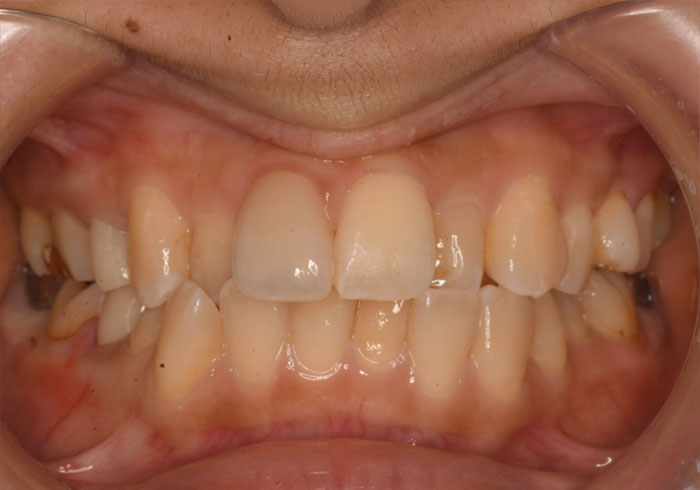

口腔内写真

治療後

マウスピース矯正 マウスピース矯正 マウスピース矯正

もともと右上前から4番目の歯が1本欠損しており、左右のバランスを合わせるために右下の歯を1本抜歯して治療を行いました。

必ずしも歯を抜かないと矯正治療ができないというわけではありませんが「笑顔やお顔とのバランス」を考慮し、今回は抜歯を提案させていただきました。